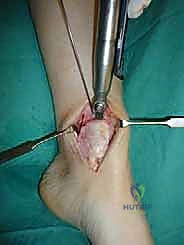

الغوص العميق: تقنية الزرع الغضروفي العظمي الذاتي (OATS) خطوة بخطوة

تُعد تقنية OATS (Osteochondral Autograft Transfer System) بمثابة "زراعة أعضاء دقيقة" داخل المفصل. الفكرة الأساسية هي أخذ أسطوانة صغيرة من العظم والغضروف السليم من منطقة لا تحمل وزناً كبيراً في جسم المريض (غالباً من مفصل الركبة)، ونقلها وزرعها في مكان الآفة التالفة في الكاحل.

هذه التقنية توفر "غضروفاً زجاجياً حقيقياً" (Hyaline Cartilage)، وهو نفس نوع الغضروف الأصلي الذي خُلق به الإنسان، مما يضمن متانة وقدرة على تحمل الأوزان لا يوفرها أي علاج آخر.